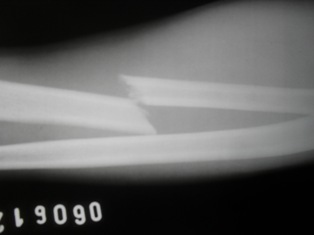

Raio X da fratura

No inicio da noite de ontem, na avenida Teotônio Freire, o João de Cleiton dos Anjos Justino, residente no Bairro Silvio Bezerra de Melo, foi atropelado quando pilotava sua bicicleta, segundo a vítima, por um Palio preto.

A vítima ainda tentou perseguir o carro atropelador e quando chegou na BR 226, próximo ao Posto Toscano, não suportou as dores e caiu na pista, sendo necessário a locomoção por uma ambulância do HPJM.

Infelizmente por se tratar de uma pessoas simples, o motorista evadiu-se do local e até agora não apareceu para ter noticia da vítima.